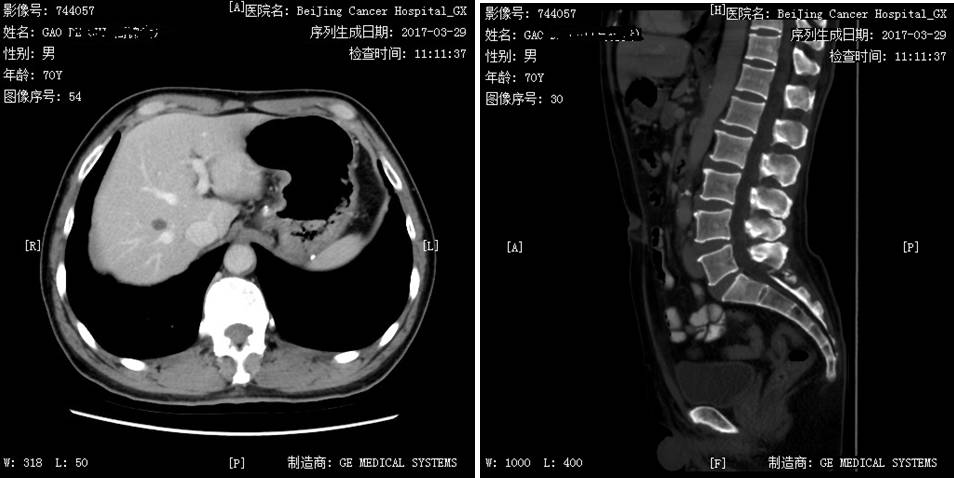

患者于1998年行右肾透明细胞癌术,术后行干扰素治疗1月余,2009年发现双肺多发占位,2009年11月开始口服培唑帕尼800 mg QD治疗。治疗2周期病灶缩小,治疗4周期达疾病稳定(SD),治疗期间出现肝损3度、血压升高、口腔黏膜炎、腹泻1~2度,培唑帕尼减量至600 mg口服治疗,疾病持续稳定。迄今患者术后已累计生存达18年,累计应用培唑帕尼治疗7年,生存状况良好。 姓名:高某 性别:男性 年龄:74岁 患者1998年行右肾透明细胞癌术,术后行干扰素治疗1月余。2009年因憋气/胸闷于石景山医院就诊。2009年10月19日,行胸部增强CT检查发现双肺多发结节,左肺门肿大淋巴结,纵隔小淋巴结,腹部改变,结合病史考虑转移,并建议进一步追查(图1)。2009年10月20日,行腹部CT发现腰3椎体骨转移(图2)。于2009年11月入北京肿瘤医院就诊。既往血糖升高。 图1 2009年10月19日胸部CT检查 双肺纹理走行顺畅,肺内透亮度均匀,双肺见多发大小不等结节,较大约28×23 mm(IMA26),未见肺内结节或斑片影;纵隔4组见小淋巴结,小于10 mm,左肺门见一肿大淋巴结,约26×21 mm(IMA42);锁骨上区及双腋下未见肿大来不及;双侧胸膜稍增厚,未见胸水征象;扫及发现双肺多发占位胸廓诸骨未见明确破坏征象;胃小弯可见一淋巴结,约1 cm(IMA13)。 图2 2009年10月20日腹部CT检查 口服培唑帕尼800mg QD治疗2周期复查病灶有缩小,治疗4周期疗效评价为SD(缩小)。治疗期间患者出现3度肝损伤(最高(ALT221iu/l)、血压升高、口腔黏膜炎、1~2度腹泻。考虑肝损害,予以减量至600mg Qd治疗,未再出现肝转氨酶显著升高,期间出现甲状腺功能减退,甲状腺素替代治疗未诉不适,每3个月复查,疗效评价均为SD。2017年4月21日,体格检查一般情况可,心肺未见异常。肿瘤复查未见增大。 2017年3月复查病灶大致同前,胃小弯淋巴结基本消失,腰3转移消失(图3)。 图3 2017年3月29日复查腹部CT:胃小弯淋巴结基本消失,腰3转移消失 肾透明细胞癌是最常见的肾脏肿瘤,约30%的患者在诊断时已经发生转移。目前晚期肾透明细胞癌的治疗已经是靶向治疗时代,其中主要以酪氨酸激酶抑制剂(TKI)为主,国内先后上市了索拉非尼、舒尼替尼、依维莫司、阿昔替尼、培唑帕尼等,其中,培唑帕尼与舒尼替尼是获得1类循证医学推荐的一线治疗用药,二者在既往的临床Ⅲ期研究中与安慰剂或干扰素相比,均显示了无进展生存(PFS)的获益,并得到了国内外众多指南的一致推荐。对于这两种药物临床如何选择呢?Robert J. Motzer等实施了一项全球多中心临床Ⅲ期随机对照研究,即COMPARZ研究。 该研究自2008年8月至2011年9月在北美、欧洲、澳大利亚和亚洲的14个国家(包括中国)共纳入1110例患者,以1︰1随机分组,分别给予培唑帕尼800 mg/d连续治疗(557例)或舒尼替尼4/2方案(4周50 mg/d,停药2周,553例)。结果显示,培唑帕尼的PFS非劣于舒尼替尼,研究者评审的中位PFS为:10.5个月和10.2个月。两组OS相当,培唑帕尼和舒尼替尼组分别达28.4个月和29.3个月,而培唑帕尼组的肿瘤应答率显著更高。与培唑帕尼组相比,舒尼替尼组患者有更高的疲劳(55%对63%)、手足综合征(29%对50%)和血小板减少症(41%对78%)发生率;而培唑帕尼组患者的丙氨酸氨基转移酶(ALT)水平升高率则高于舒尼替尼组(60%对43%)。在治疗前6个月14种健康相关生活质量较基线的比较中,培唑帕尼组有11种有显著优势,尤其是在疲劳或口腔、喉咙、手或足疼痛等方面,给患者带来了更高的生活质量和治疗满意度。该研究最终结果于2013年在《新英格兰医学杂志》发表,从而改写了晚期肾癌的临床治疗实践。 对于晚期肾癌的总体预后,靶向治疗的中位总生存时间为26-30个月左右,通常一线靶向药物治疗时间为1年左右,对于肺转移患者可以延长至2年左右,而该患者进入COMPARZ研究接受培唑帕尼治疗,持续接受培唑帕尼治疗迄今已累计治疗7年余,疗效评估持续维持缩小的SD,肿瘤获得良好的控制,生活质量良好,证实了培唑帕尼在临床实践中的良好疗效。也为肾透明细胞癌患者的临床一线靶向药物选择提供了有力的参考。 盛锡楠教授 副主任医师,副教授,硕士研究生导师,北京大学肿瘤医院肾癌黑色素瘤内科副主任。长期从事肿瘤内科临床和科研工作,擅长肾癌、膀胱癌、前列腺癌等泌尿肿瘤以及黑色素瘤的内科治疗。担任《中国肾癌诊治指南?2015版》执笔人,CSCO青委、CSCO肾癌专家委员会秘书,中国抗癌协会泌尿男生殖肿瘤专业委员会青委,北京抗癌协会泌尿男生殖肿瘤专业委员会委员兼秘书,CGOS分子靶向分委会常委。病例摘要